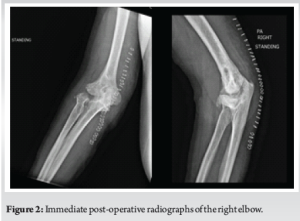

A 50-year-old right-hand dominant male presented to the orthopedic office for evaluation of chronic right elbow pain. He states this has been ongoing since he sustained an injury, while in the military, about 7 years ago. Over this period, he underwent 7 different surgeries related to this injury, with the most recent procedure in January of 2011. He noted considerable pain, stiffness, and significant difficulty performing tasks at work and activities of daily living. His pre-operative Visual Analog Scale (VAS) pain score was a 10 out of 10, mayo elbow performance score (MEPS) was 15/100 (<60 indicating poor performance), American shoulder and elbow surgeons (ASES) score of 18/100, and disabilities of the arm, shoulder and hand (DASH) score of 70/100 with additional noted severe difficulty performing his required work activities as a sports photographer. He also indicated that he was unable to participate in bowling, his sport of most importance, on pre-operative questionnaires. Radiographs and a computed tomography scan were obtained, which demonstrated advanced degenerative changes in the radiocapitellar and ulnohumeral joints (Fig. 1). Given his age, job requirements, and lifestyle, we felt the patient would not be a great candidate for a total elbow replacement given the activity and post-operative weight restrictions. Instead, we recommended treatment with an interpositional arthroplasty for the treatment of his post-traumatic osteoarthritis (Figs. 2 and 3).